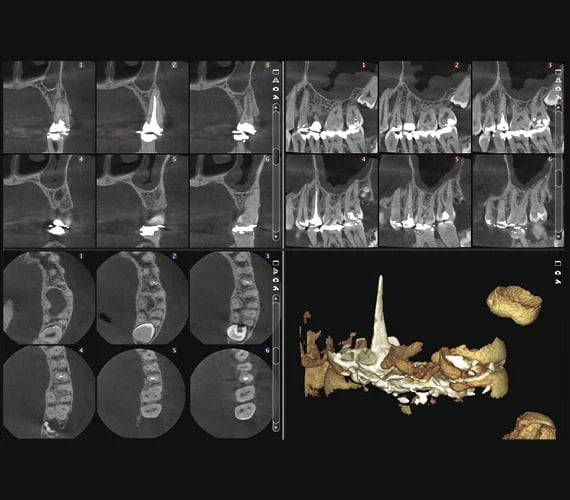

Obrazy kliniczne

Planmeca ProMax 3D Classic

Naruszony kieł

8x8

Implantologia

Ząb mądrości

Implant 3D z koroną

3 x 3D = CBCT + ProFace + skan wycisku